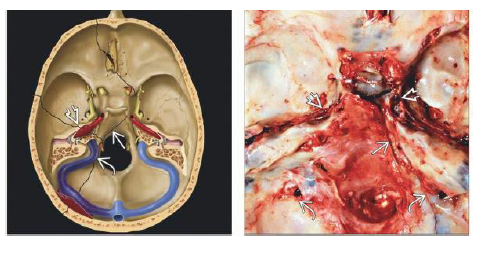

What structures are affected?

Axial graphic depicts different basilar skull fractures crossing the petrous apex and clivus , as well as extending into the jugular foramen and carotid canal

What is shown?

Axial bone CT shows skull base fractures that involve the clivus , left sigmoid sinus , and jugular foramen . Note hemotympanum . AP view of MR venogram in the same patient shows occlusion of the distal left transverse and sigmoid sinuses, jugular bulb.